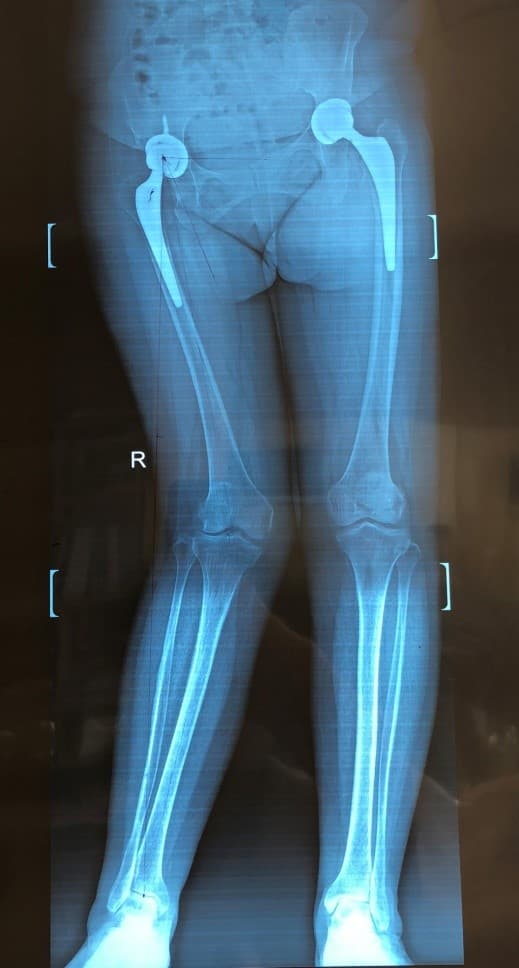

Түнхний төрөлхийн дутуу хөгжил, мултралын улмаас хоёр түнхний үеийг солих мэс засал хийгдсэн эмчлүүлэгчид хийгдсэн саруй хөл засах мэс заслын өмнөх болон дараах рентген зураг

Саруй хөл нь ихэвчлэн өвдөгний гадна хэсэгт ирэх ачааллыг нэмэгдүүлж өвдөлт зовиур үүсгэдэг тул засагдсанаар өвдөгний остеоартритын явц удааширч, өвдөлт зовиур арилж, хөл тэгширч, хөлийн урт богины зөрүү багасдаг.